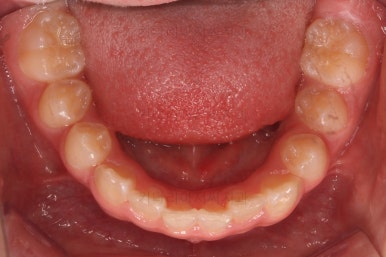

초진 시 입안의 모습입니다.

전반적으로 치열이 삐뚤삐뚤하고요.

오른쪽 상단 사진을 보시면 어금니의 높이와 앞니의 높이가 차이가 많이 납니다.

앞니가 솟구쳐 있는 양상인데요.

그 이유 때문에 어금니로 다물었을 때의 위아래 앞니가 많이 겹쳐서 아래 앞니가 아예 보이지 않는 상황이었어요.

이를 "과개교합"이라고 표현합니다.

그리고 전반적으로 아래 치열이 윗니에 비해 뒤로 밀려 있어서, 어금니의 맞물림이 좋지 못하고 듬성듬성해 보이는 상황이었어요.